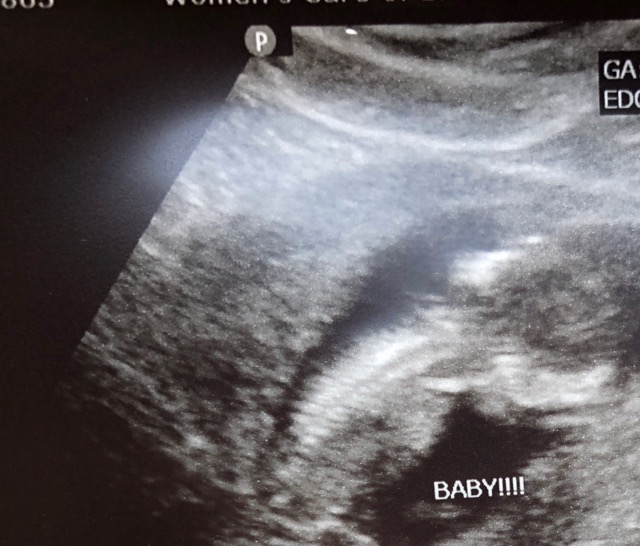

13 weeks 3 days on this ultrasound ❣️ baby only wants to show it’s back right now 🙄🤦🏽♀️. We love this little one so much already 💓